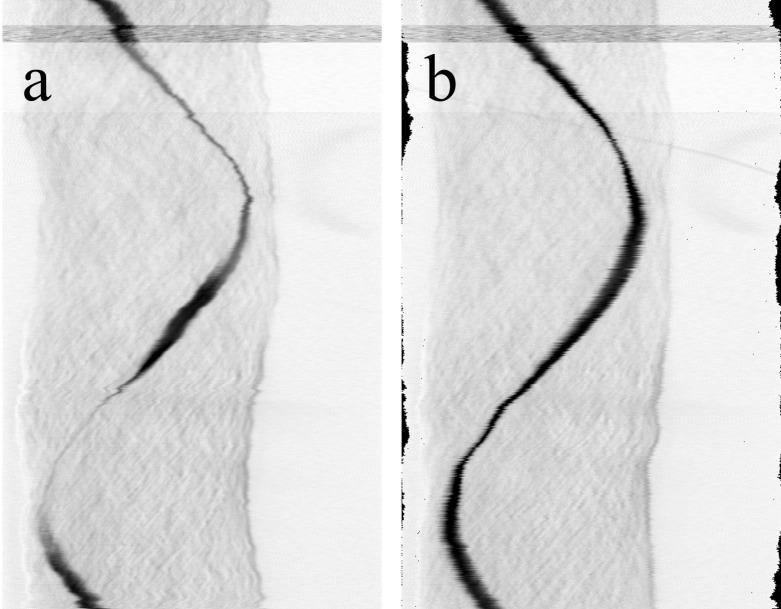

用于扫描激光光学断层扫描的自动样本跟踪和参数适配

Automated sample tracking and parameter adaption for scanning laser optical tomography.

Non-destructive, three-dimensional imaging techniques are of great importance in medicine as well as in technical analysis. In this context, it is of particular importance to generate reliable and repeatable results of high quality. This can be aided by automation of manual processes. One of these imaging techniques, the Scanning Laser Optical Tomography, currently requires manual sample alignment by the user to achieve the highest possible image quality. This alignment demands skillful hand-eye coordination as well as experience on the part of the user, and thus often leads to inconsistent imaging results. To overcome this problem, this paper presents a technique for software-based automation of this challenge. The sample is not physically aligned, but digitally detected and tracked during the acquisition. Residual motion artifacts that interfere with tomographic reconstruction are corrected using a second automation algorithm. The combination of the two new algorithms significantly improves the quality of imaging and also increases the reliability and degree of automation of the system, making it accessible to a wide range of users.

无损三维成像技术在医学以及技术分析中都非常重要。在这种背景下,生成高质量的可靠且可重复的结果尤为重要。手动过程的自动化可以对此提供帮助。这些成像技术之一,即扫描激光光学断层扫描,目前需要用户手动对齐样本以获得尽可能高的图像质量。这种对齐需要熟练的手眼协调能力以及用户的经验,因此常常导致成像结果不一致。为了克服这个问题,本文提出了一种基于软件的自动化技术来应对这一挑战。样本不是进行物理对齐,而是在采集过程中进行数字检测和跟踪。使用第二种自动化算法校正干扰断层重建的残余运动伪影。这两种新算法的结合显著提高了成像质量,还提高了系统的可靠性和自动化程度,使广大用户都能够使用该系统。